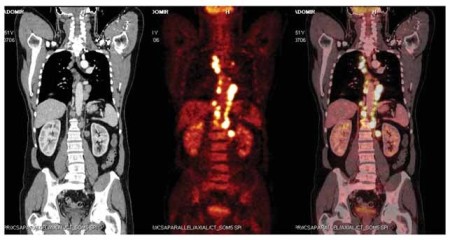

Obr. 1: Postižení lymfatických uzlin u nemocného s difúzním

B-velkobuněčným lymfomem - snímky pořízené počítačovou tomografií

(CT), pozitronovou emisní tomografií (PET) a integrovaným PET/CT

vyšetřením za použití 2-[fluorin-18]

fluoro-2-deoxy-D-glukózy.